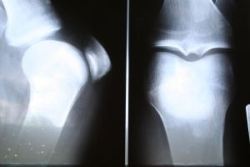

Denzitometria (DEXA – viď obr.) je testom špecializovaného typu, ktorý je presný, nebolestivý a nezáťažový pre pacienta. DEXA umožňuje zmeranie kostnej hmoty v ktoromkoľvek úseku kostry (obyčajne v oblasti bedrovej chrbtice, stehnovej kosti, dolnej časti predlaktia = miesta typických osteoporotických zlomenín) počas necelej polhodiny, pri minimálnej radiačnej záťaži (pod 5 mrem). Táto radiačná záťaž zodpovedá približne letu lietadlom a môžeme ju považovať za takmer zanedbateľnú. K denzitometrickému vyšetreniu nie je nutná špeciálna príprava pacienta. Meraním sa stanoví množstvo kostného minerálu a toto stanovené množstvo je porovnané s hodnotami, ktoré sa nachádzajú u mladých zdravých žien. Rozdiel medzi týmito hodnotami sa vyjadruje v hodnotách tzv. T-skóre, ktoré nás informuje o koľko je hodnota u vyšetrovanej osoby nižšia. Tzv. Z-skóre porovnáva hodnotu pacienta s hodnotami u rovnako starých zdravých osôb. Porovnanie sa vyjadruje v smerodajných odchýlkach od priemeru.

S klesajúcimi hodnotami denzitometrických parametrov stúpa riziko osteoporotických zlomenín. Naopak pri správnej liečbe aj malý nárast kostnej hmoty zistený kontrolným denzitometrickým vyšetrením, je prejavom zlepšenia pevnosti kostí a dochádza k zníženiu rizika osteoporotických zlomenín. Denzitometria teda dokáže odhaliť aj včasné štádiá rednutia kostí a pri kontrolných vyšetreniach nás informovať spolu s ďalšími metodikami o úspešnosti komplexnej liečby (viď obr. Nález denzitometrického vyšetrenia).

Pri obyčajnom röntgenovom vyšetrení nie je možné osteoporózu zistiť, pokiaľ nedôjde k úbytku kostnej hmoty najmenej o 20 až 30 percent. Takže pre včasné odhalenie osteoporózy nemá táto metodika význam, má však prínos pri diagnostike zlomenín stavcov a vylúčení sekundárnych príčin osteoporózy, napr. pri nádoroch.